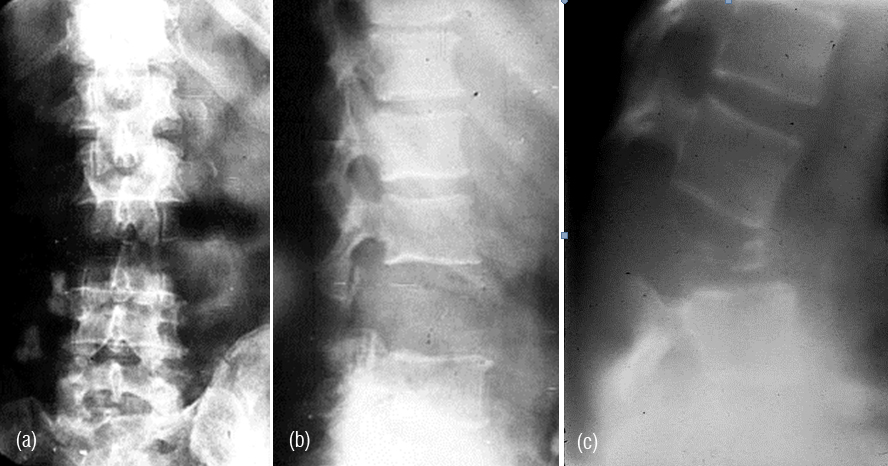

Figure 3abc: Plasmacytoma - Complete destruction of body of L3 including the posterior elements.

Figure 4a,b,c: CT - Plasmacytoma of sacrum, an expanding lytic lesion.